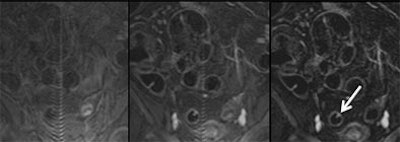

| Three views of the colon in a 48-year-old patient with a single polyp are seen at different time points: 1) without contrast material (left); and 2) following intravenous injection of 0.2 mmol/kg Gd-DOTA (Dotarem). This view shows good uptake of contrast material to the colon wall, and especially to the polyp (middle). Image at right 3) shows subtraction of the plain from the enhanced image, providing optimal visualization of regions with contrast uptake. Residual stool has also been subtracted, rendering the colonic lumen homogeneously dark. Images courtesy of Dr. Christoph Herborn. |